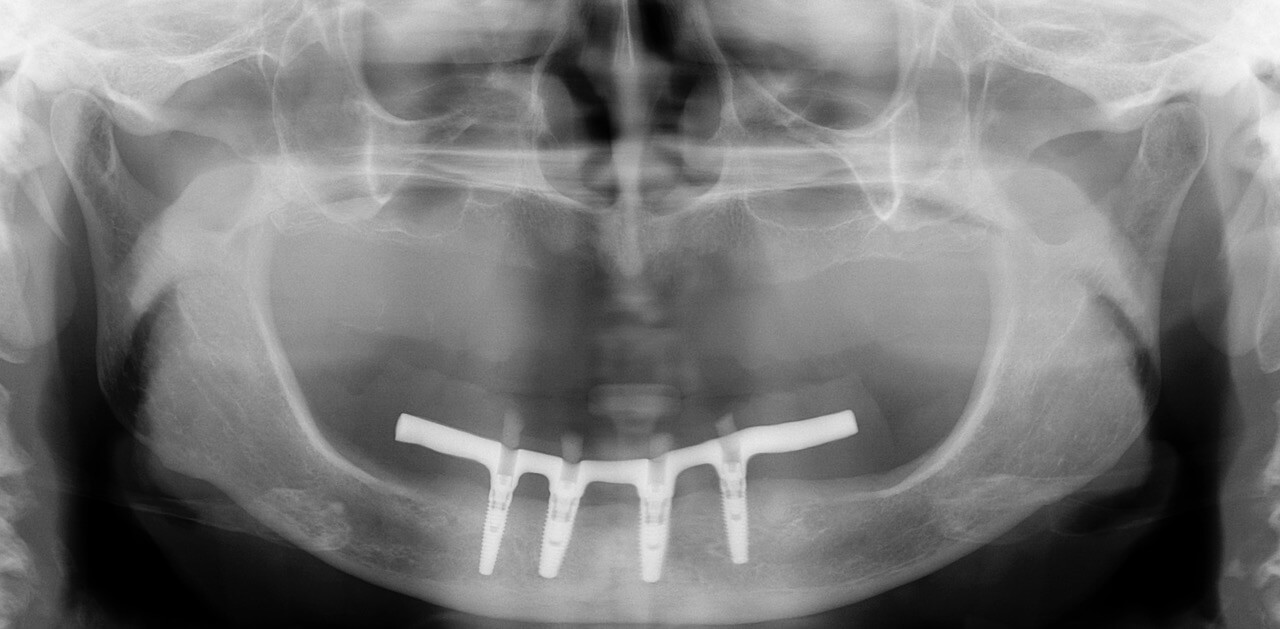

Обратилась с жалобами на отсутствие зубов. Было проведено лечение с установкой 4х имплантатов системы Нобель. Изготовлен условно съемный протез на винтовой фиксации на нижнюю челюсть и полный съемный протез на верхнюю челюсть.